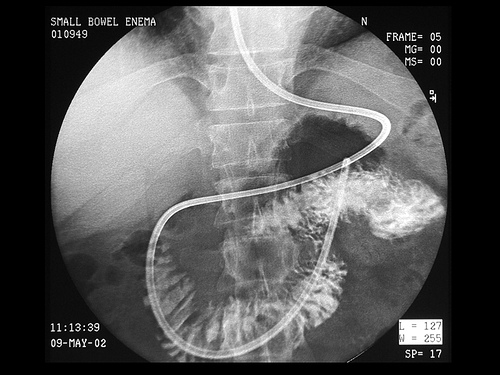

β) Εντερόκλυση: Εισάγεται σκιαγραφική ουσία κατευθείαν στο λεπτό έντερο με τη βοήθεια καθετήρα. Η μέθοδος υπερέχει των άλλων δύο εξετάσεων, γιατί η πλήρωση του λεπτού εντέρου δεν εξαρτάται από την κένωση του στομάχου, η ταχύτητα διέλευσης του βαρίου από τις έλικες επηρεάζεται από την ταχύτητα χορηγήσεως και επιτυγχάνεται ικανοποιητική διάταση του εντέρου.